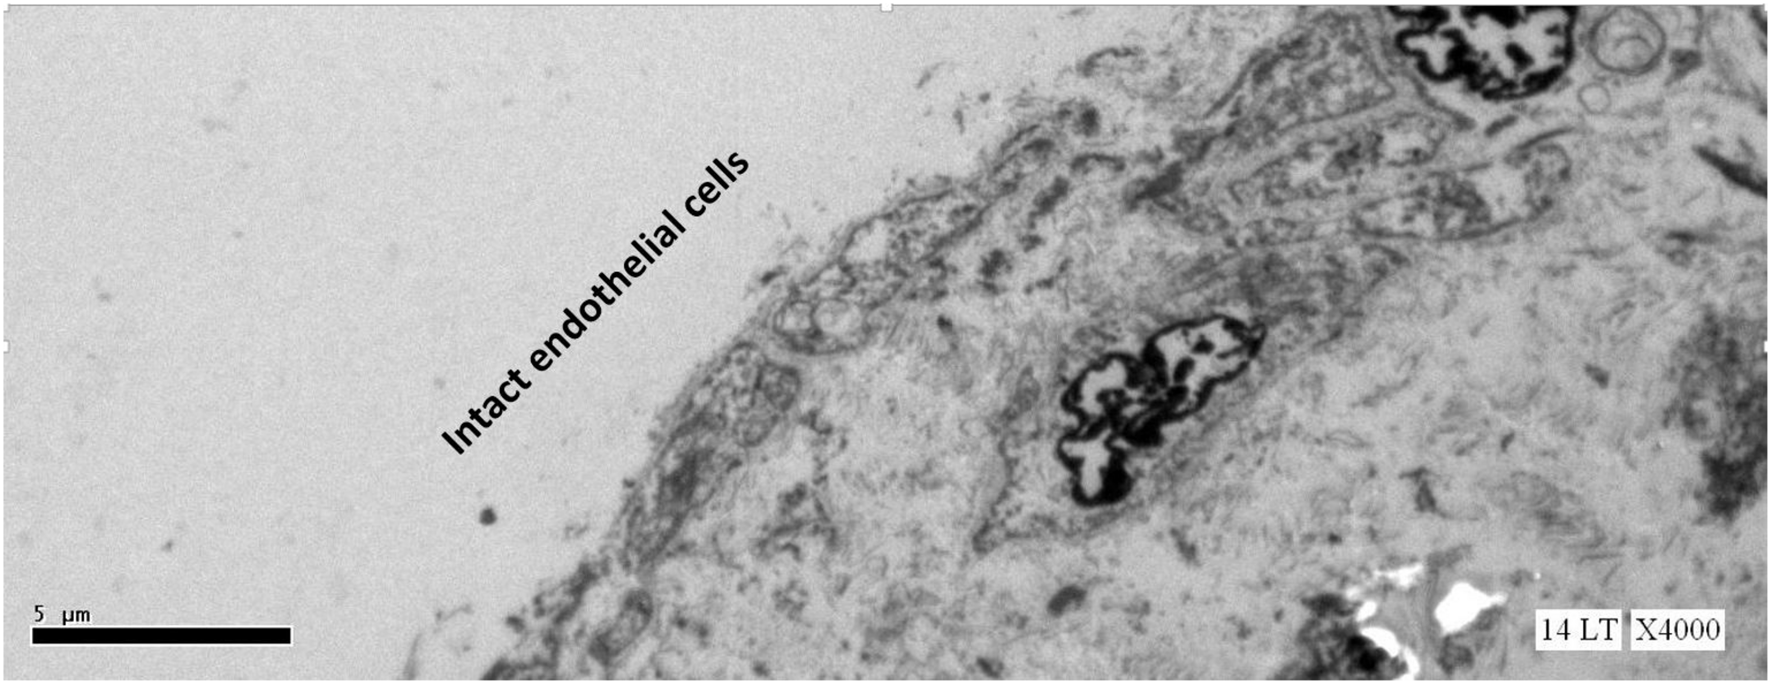

This study expected to observe the breaches in the oligolamellar lining of the phospholipids at the AHS. However, in the first few samples from the AHS, no endothelial cells were seen at the luminal side of the blood vessel. For denial of the wrong sampling, this study let the professional staff at the pathology department to make the sampling. Again, no endothelial cells were observed, but the elastin layer of the intima adjacent to the media was observed at the AHS (Figure 2) with some debris from the teared endothelial layer. Intact endothelial cells were observed only in the samples of the control area, distant from the AHS (Figure 3). Detaching bubbles teared off the entire endothelial layer at the AHS. Detachment of an entire endothelial layer led us to turn to observation with the LM.

FIGURE 3

Electron microscopy view of the luminal aspect of the blood vessels at a control site (away from the AHS). Intact endothelial cells are seen.